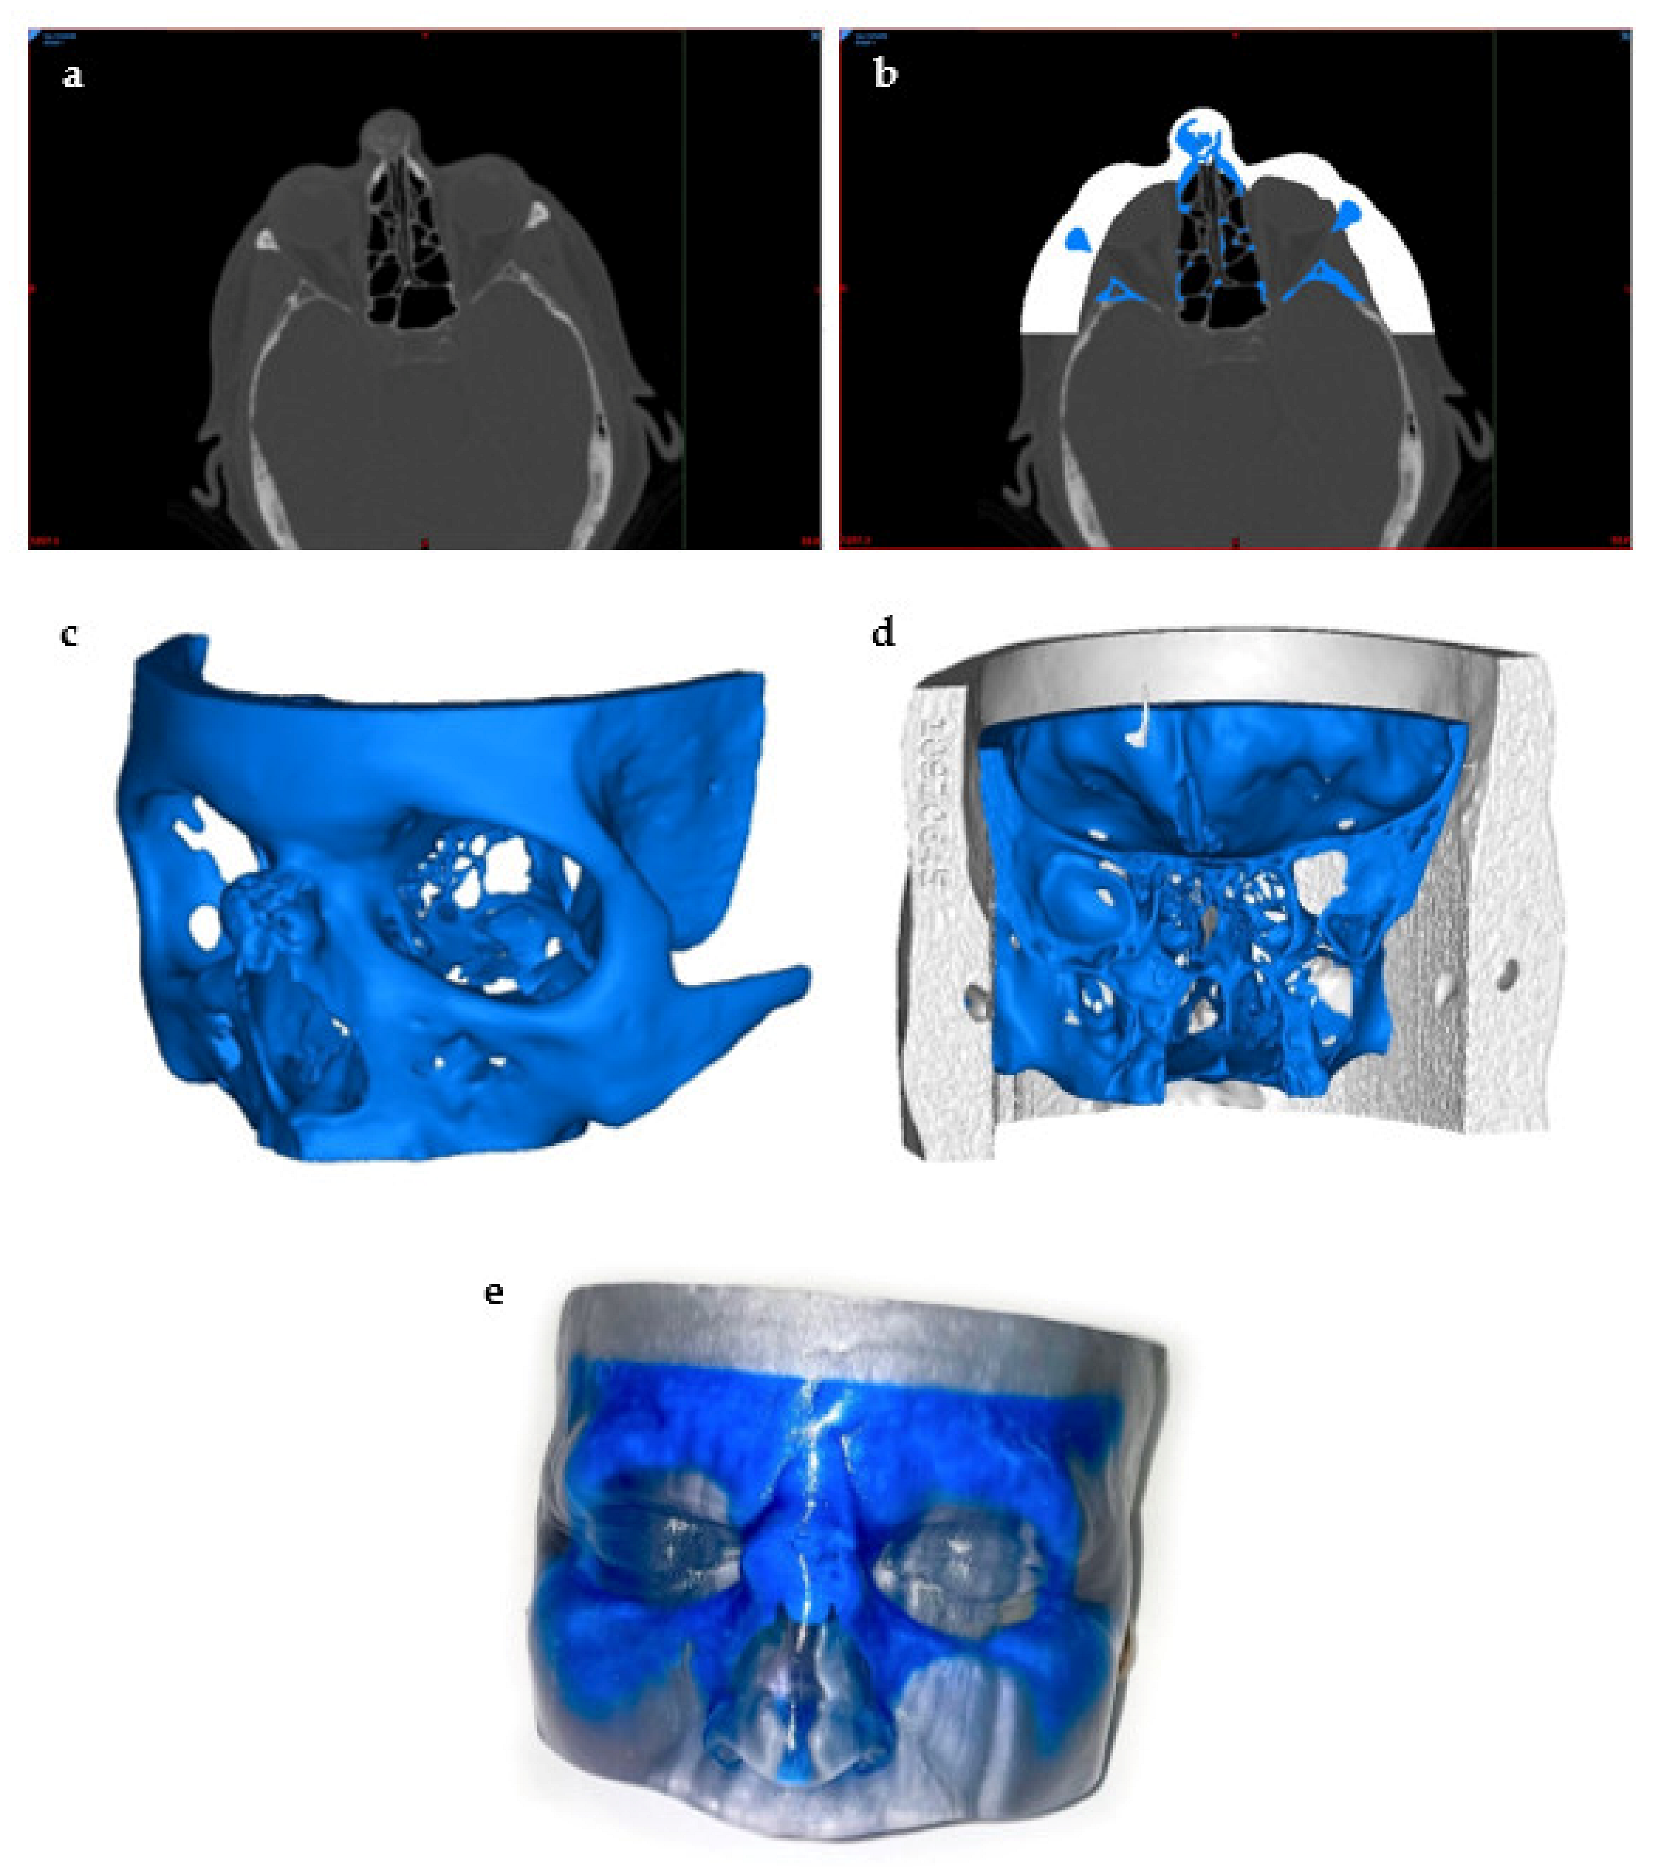

5.1.1. Image Acquisition

5.1.2. Designing the 3D Model

- Mitsouras, D.; Liacouras, P.; Imanzadeh, A.; Giannopoulos, A.A.; Cai, T.; Kumamaru, K.K.; George, E.; Wake, N.; Caterson, E.J.; Pomahac, B.; et al. Medical 3D Printing for the Radiologist. Radiographics 2015, 35, 1965–1988. [Google Scholar] [CrossRef]

- Chepelev, L.; Wake, N.; Ryan, J.; Althobaity, W.; Gupta, A.; Arribas, E.; Santiago, L.; Ballard, D.H.; Wang, K.C.; Weadock, W.; et al. Radiological Society of North America (RSNA) 3D printing Special Interest Group (SIG): Guidelines for medical 3D printing and appropriateness for clinical scenarios. 3D Print. Med. 2018, 4, 11. [Google Scholar] [CrossRef]

- Filippou, V.; Tsoumpas, C. Recent advances on the development of phantoms using 3D printing for imaging with CT, MRI, PET, SPECT, and ultrasound. Med. Phys. 2018, 45, e740–e760. [Google Scholar] [CrossRef]

- Datta, P.; Barui, A.; Wu, Y.; Ozbolat, V.; Moncal, K.K.; Ozbolat, I.T. Essential steps in bioprinting: From pre- to post-bioprinting. Biotechnol. Adv. 2018, 36, 1481–1504. [Google Scholar] [CrossRef]